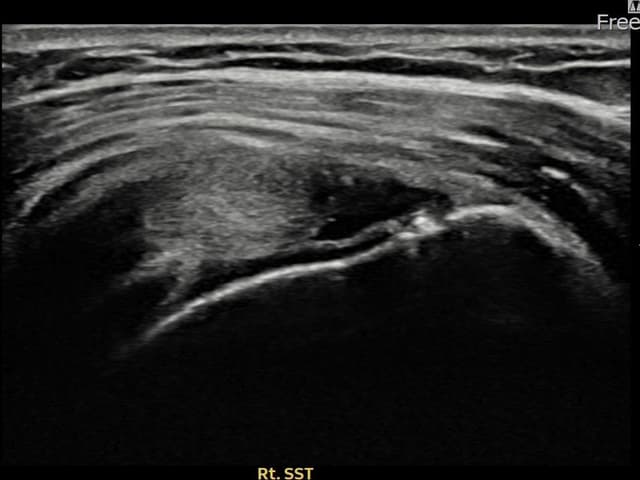

[촬영시기:21.09.27~21.10.07]

[석회분쇄흡입술] 우측 어깨의 야간 통증과 운동 제한으로 수개월간 고통받다 내원한 50세 남성 환자로, X-ray에서 극상근건 내 석회 침착이 확인되어 석회분쇄흡입술을 시행하였습니다.